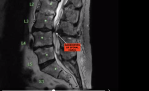

Have had the problem twice, latest was in early 2017, pain in left leg, gradually got worse to almost unbearable. To GP arranged an MRI same problem as on right leg 19 years earlier, SPINAL STENOSIS, narrowing of the Spinal Canal where the wiring harness passes through, (Spinal Cord), vertebrae pressing on a nerve.

Went to Spinal Specialist in Brisbane, (Bris Brain & Spine), who had done other side, 3 ½ hours surgery and like new again after a couple of months. Have more flexibility now than for years.

Removed offending piece of Vertebrae, fused 2 vertebrae, inserted 6 screws and plastic cage around it all. Previous occasion was on left leg 19 years earlier and he only needed to trim vertebrae on that occasion.

XRAY SPINE 1 2019-08-30 at 9.27.29 am.png

-- Edited by blissonwheels on Monday 22nd of June 2020 10:22:52 AM